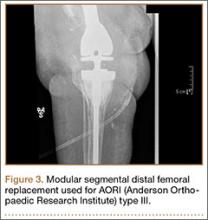

5. Modular segmental arthroplasty designs

Segmental arthroplasty prostheses, which typically are end-of-the-line revision TKA options, are applicable only in cases of extensive bone loss (more than can be treated with allografts or augments; AORI type 3), complete ligamentous disruption/absence, loss of periprosthetic soft tissue, and multiple previous revision procedures (Figure 3). Despite the limited indications for these prostheses, they yield quick return to function without graft nonunion or resorption, and they augment ingrowth/ongrowth. Furthermore, the next surgical option could be fusion or amputation. When failures were specifically evaluated for aseptic loosening across 4 studies, the survival rate ranged from 83% to 99.5%, with the most frequent complication being infection (up to 33% in one series).6,19-21

The major roles for segmental arthroplasty prostheses in primary TKAs are in the setting of oncologic conditions that require bony excision, or unreconstuctable fractures about the knee. Used after ancillary metastatic disease, these prostheses demonstrate positive results, according to several reports.22,23 In the setting of revision TKA, however, these prostheses should be used only when other surgical options are unfeasible, given the high risk for infection and the re-revision rates. Currently, revision TKAs with tumor prostheses have a high failure rate (up to 50%) because of the extensive surgery and the lack of bony and soft-tissue support (Table 2).